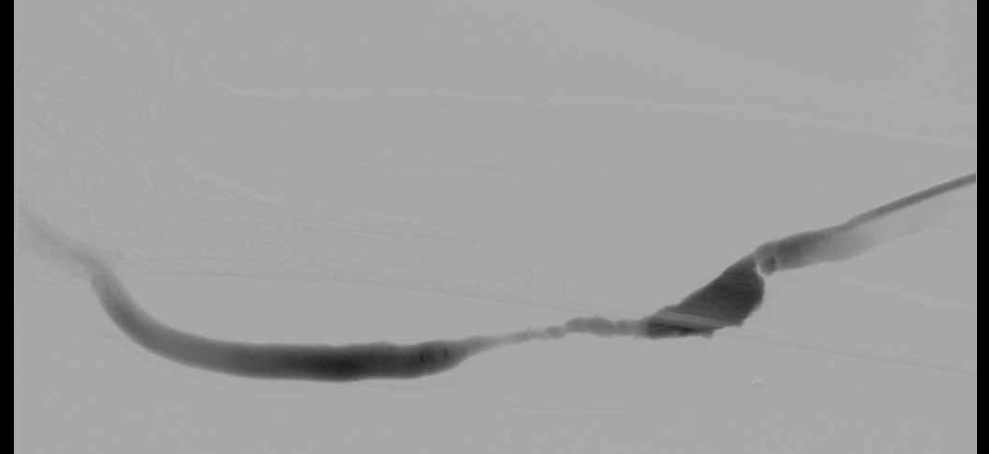

시술 전

시술 후